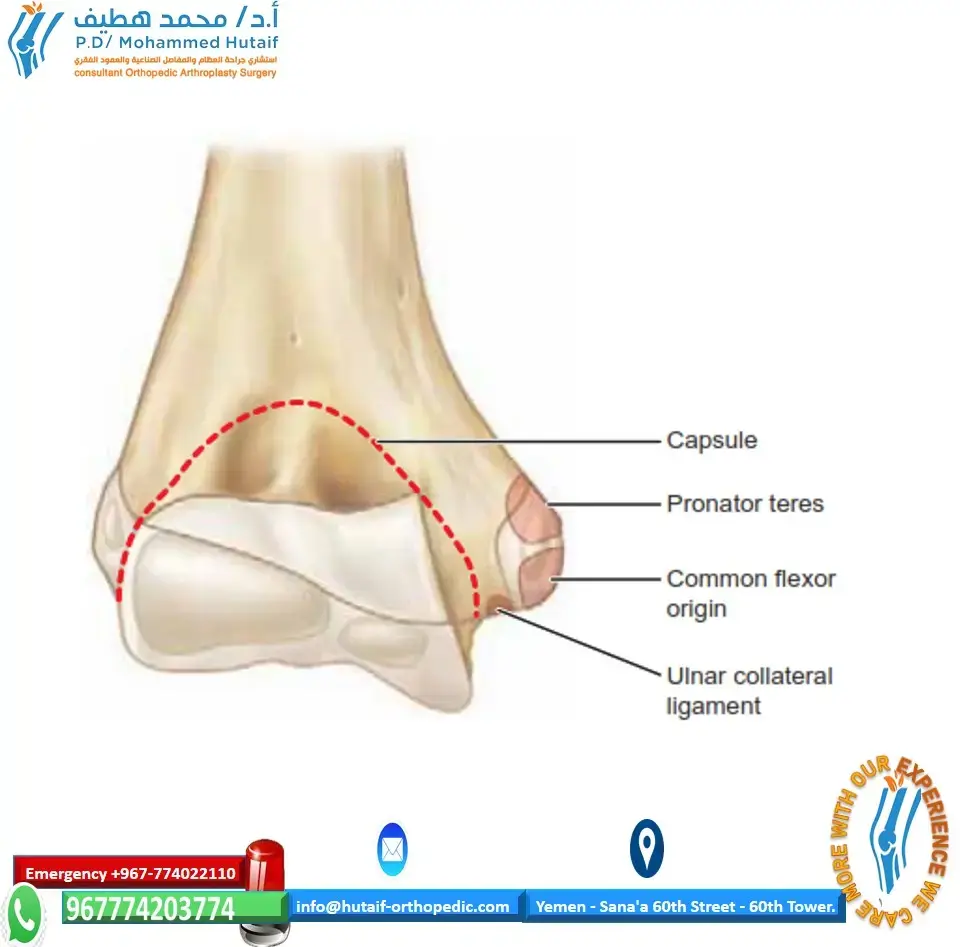

لفهم إصابة مفصل الكاحل الرباطي، من الضروري أولاً استيعاب التركيب التشريحي المعقد لمفصل الكاحل. يُعد الكاحل مفصلاً محوريًا يربط الساق بالقدم، ويتكون أساسًا من ثلاثة عظام رئيسية:

تتصل هذه العظام معًا بواسطة شبكة قوية من الأربطة التي توفر الاستقرار وتحد من الحركة المفرطة. الأربطة الرئيسية المعنية بإصابة مفصل الكاحل الرباطي هي:

الأربطة الظنبوبية الشظوية (Syndesmotic Ligaments)

هذه الأربطة هي التي تربط الجزء السفلي من عظمي الظنبوب والشظية معًا، وتشكل ما يُعرف بالرباط الظنبوبي الشظوي. تُعد هذه الأربطة حاسمة لاستقرار مفصل الكاحل، وتشمل:

الرباط الدالي (Deltoid Ligament)

الأربطة الجانبية (Lateral Ligaments)

يُشكل التفاعل بين هذه العظام والأربطة "المدقة" أو "الشوكة" (Mortise) التي تُثبت عظم الكاحل في مكانه، مما يسمح بحركة الانثناء الظهري والأخمصي للقدم. عندما تتضرر الأربطة الظنبوبية الشظوية، يحدث تباعد بين الظنبوب والشظية، مما يؤدي إلى عدم استقرار المدقة بأكملها، وهذا ما يُسبب الألم الشديد والمضاعفات طويلة الأمد إذا لم يتم علاجه بشكل صحيح.